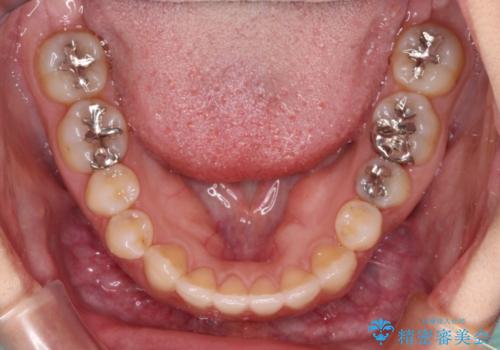

開咬と変色した前歯 インビザライン矯正とオールセラミッククラウン治療

- 前歯の開咬と失活により変色した前歯を気にして来院された患者様です。

開咬の治療は、前歯を閉じるように引っ張り出すよりも、上下臼歯を圧下(骨内にめり込ませる)させることで進める方が長期的に安定した歯列を維持できます。

インビザラインは臼歯の圧下を効果的に行えるため、インビザラインを用いて矯正治療を行うこととしました。

矯正治療が概ね終了した時点で前歯をオールセラミッククラウンにて補綴治療を行い、その後インビザラインにて細かい部分を仕上げていくことしました。

オープンバイトは舌の突出癖により誘発され、治療後も突出癖が残っている容易に後戻りしてしまいます。

治療期間を短縮するためにも、舌突出癖の改善が極めて重要となります。